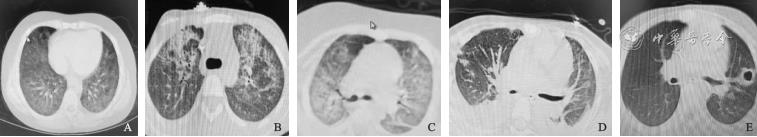

肺部CT可见4种类型(磨玻璃型、斑片型、间质型、囊变型),不同类型的病变常同时存在,见表2及图1。9例患儿均无肺门及纵隔淋巴结肿大。1例合并胸腔积液。1例死亡病例(例7)治疗过程中出现气胸、皮下气肿。

| 例1 | 两肺支气管血管束呈网格样,两肺内广泛斑片状影(肺间质改变、肺泡性水肿)(图1A) |

| 例2 | 两肺上叶及邻近下肺可见网格样致密影,呈铺路石样改变,小叶间隔增厚(肺间质改变)(图1B) |

| 例3 | 两肺支气管血管束增多、增粗,透亮度减低,两肺内可见广泛散在斑片状、条索状及磨玻璃影(图1C) |

| 例4 | 两肺支气管血管束粗乱,两肺内可见多发点片状影及磨玻璃影,部分结节性病灶,呈晕征样改变 |

| 例5 | 两肺纹理粗乱,可见条片状淡薄及致密影,双侧胸腔积液(图1D) |

| 例6 | 肺透亮度减低,两肺内可见广泛散在斑片状影及磨玻璃影 |

| 例7 | 两肺支气管束血管束增多增粗,两肺内可见点片状高密度影 |

| 例8 | 两肺支气管血管束增多增粗,左肺内可见数个囊性厚壁透亮影,其旁可见片状高密度影(图1E) |

| 例9 | 两肺支气管血管束粗乱,两肺内可见多发大片模糊影 |

A:肺间质改变,肺泡性水肿;B:铺路石样改变,小叶间隔增厚;C:磨玻璃样改变;D:条片状淡薄及致密影,合并胸腔积液;E:囊变性。

本研究患儿预后较好,8例患儿均好转出院,主要原因在于PCP的早期诊断和及时治疗。有5例患儿通过肺部CT影像结果考虑真菌感染,同时存在基础疾病,有肿瘤化疗史,在病原学结果未明确前,即开始SMZ-TMP经验治疗。因此,肺部CT的典型影像特点对PCP有重要诊断价值。PCP的影像学表现形式多样,且依病情进展而呈现不同的影像学特点,最常见可分为4种类型,包括斑片型(即肺泡实变影,表现为双侧不均匀斑片状模糊阴影,边界不清,可伴有小叶间隔或小叶内间隔网格状增厚,表现为网状影,呈马赛克样或铺路石样改变);磨玻璃型(双肺磨玻璃样密度增高影);间质型(双侧间质纹理增多,表现为双侧不对称或基本对称的弥漫网状或网织结节影);囊变型(表现为多发囊变影,多为圆形,内外壁光滑且壁厚不超过1 mm的无内容物囊腔,可相互融合,多分布于两肺上叶或肺周边,也可发展至整个肺实质的囊性改变)[10, 11]。本研究患儿的肺部CT主要以斑片型、间质型、磨玻璃型为主,且不同类型的病变常同时存在。